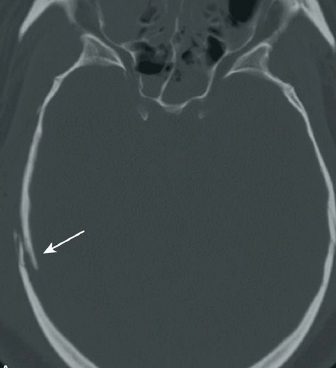

Q

TCE

¿Qué tipo de fractura es esta?

A

Fractura de base de cráneo